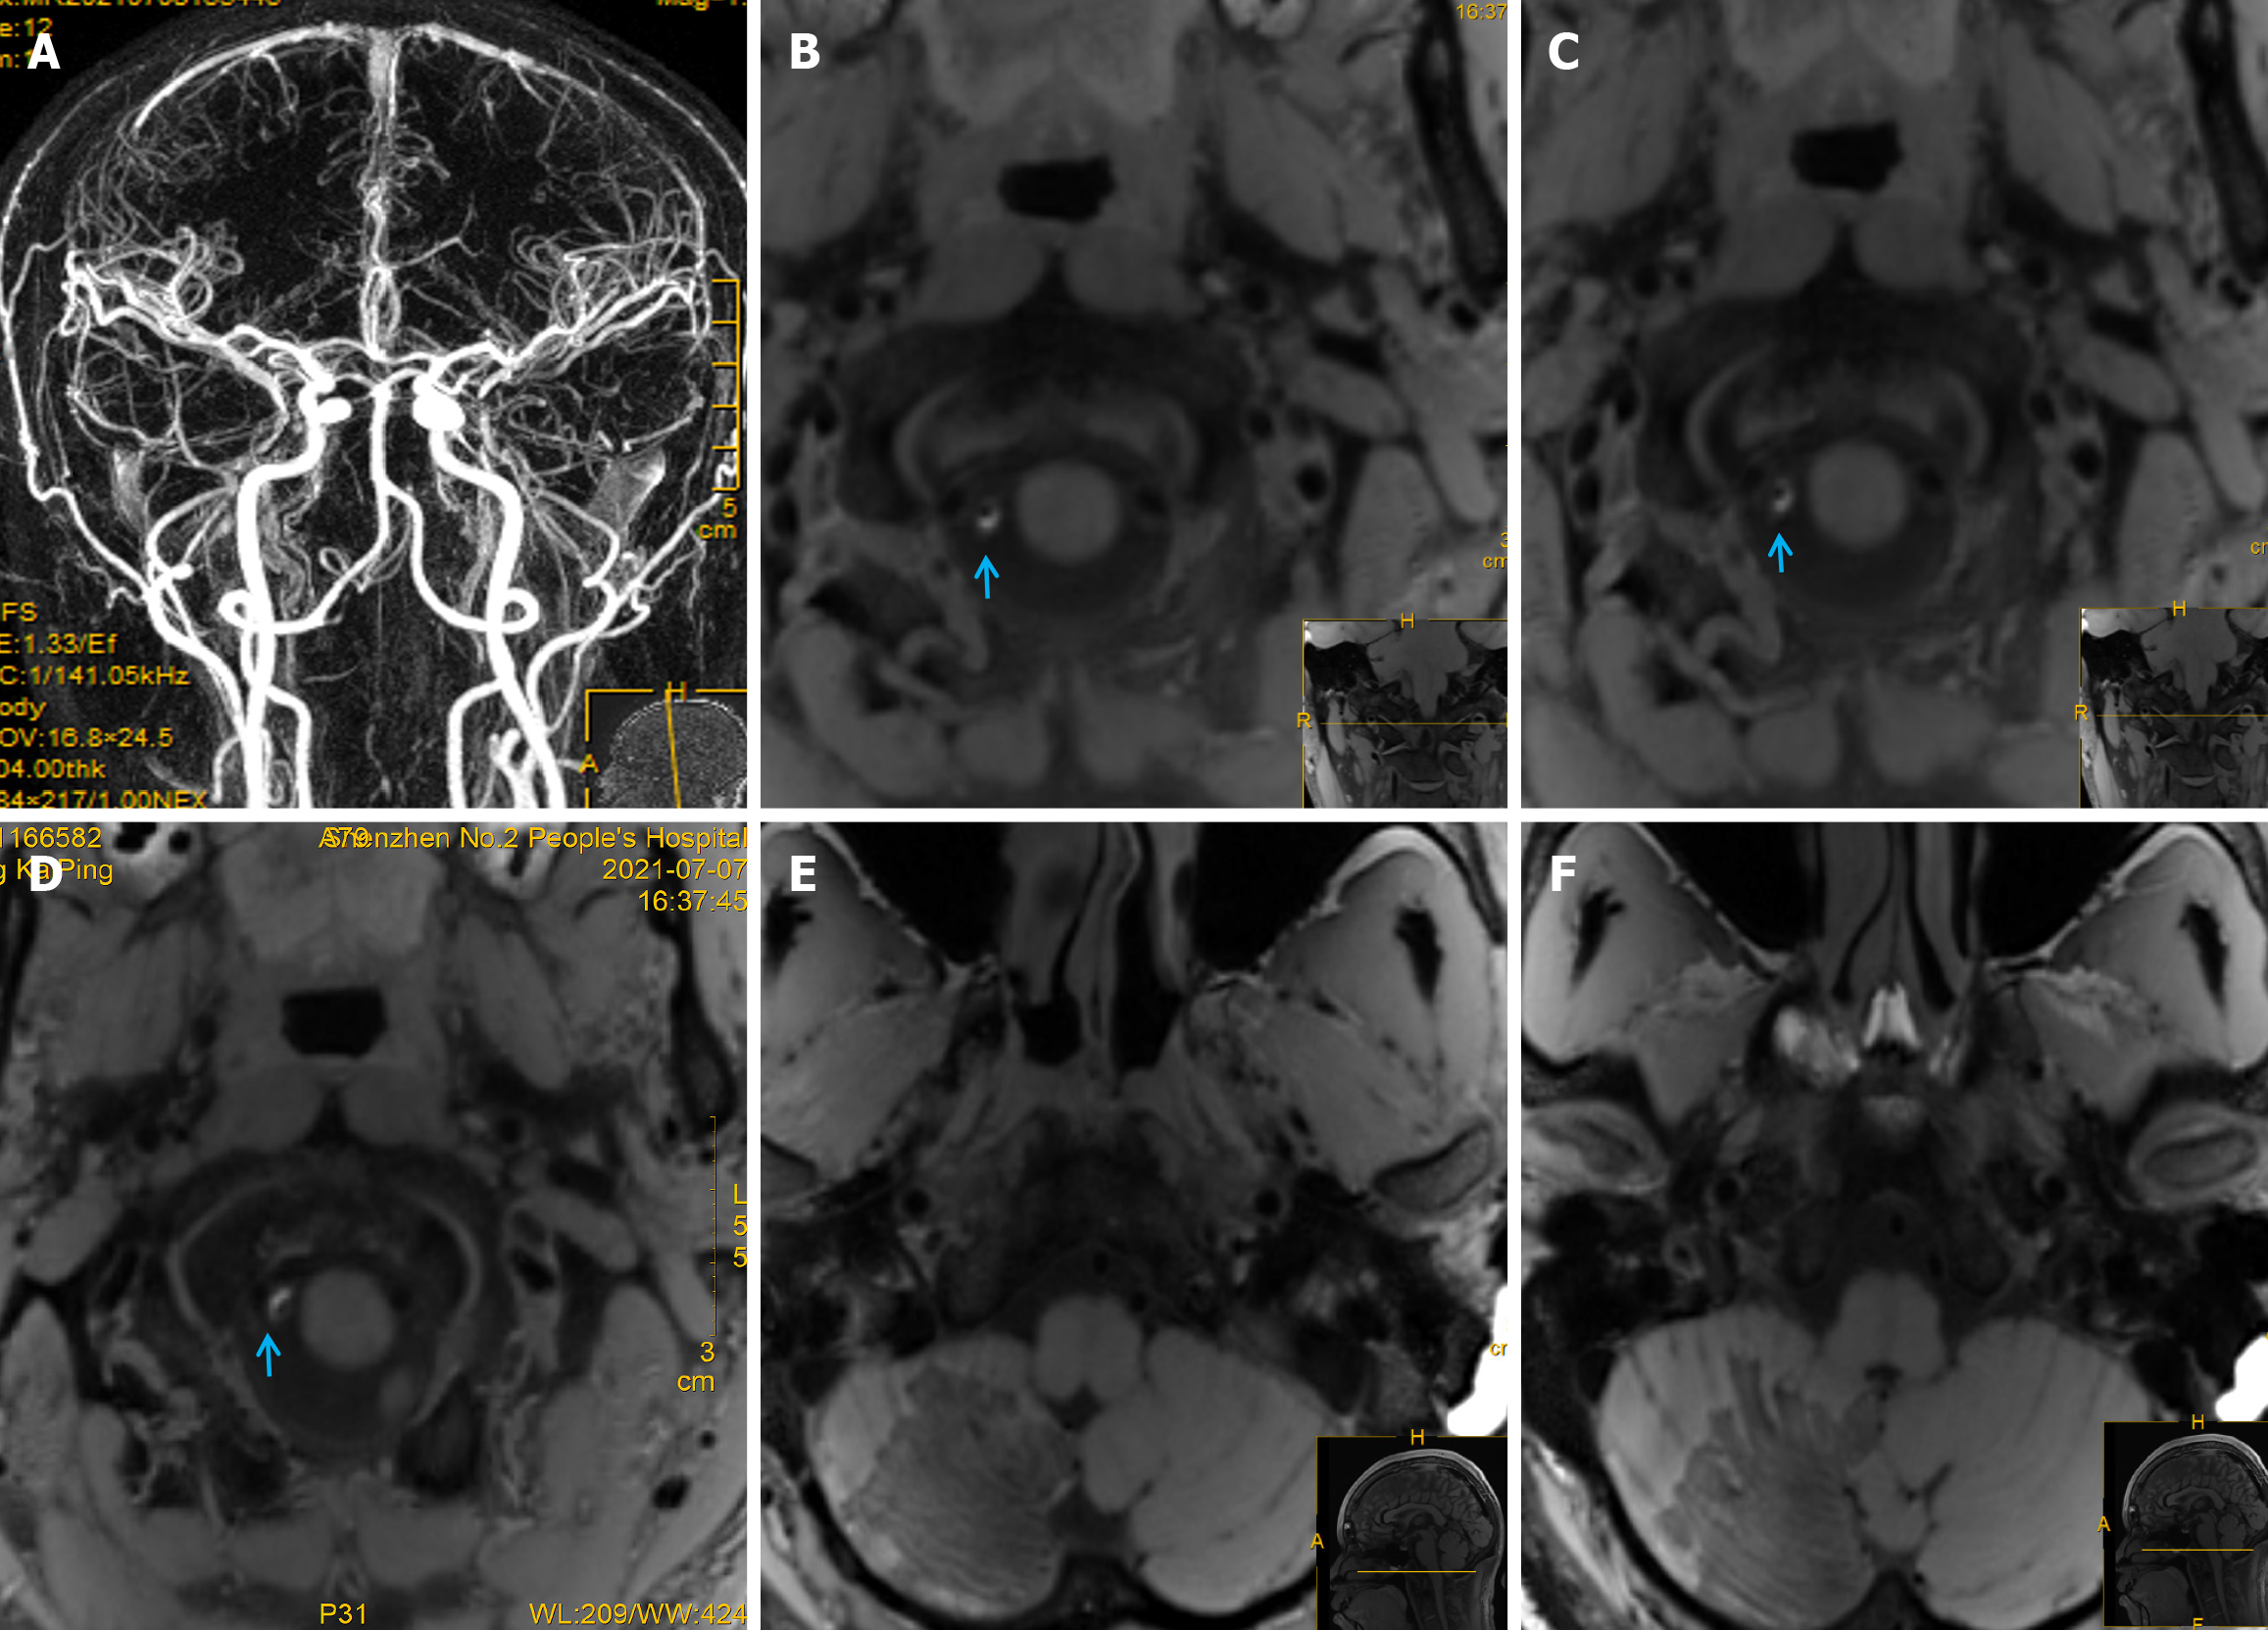

Chest CT showed scattered exudative lesions in both lungs, and bilateral lower lobes were clearly visible. Abdominal CT showed mild fatty liver, and echocardiography, contrast transcranial Doppler, contrast echocardiography, and 24-hour dynamic electrocardiography revealed obvious abnormalities. Furthermore, 1.5-T magnetic resonance imaging (MRI) showed a massive acute right cerebellar infarction (Figure 1D-I) in the area supplied by the PICA (Figure 1J)[7], with no obvious abnormalities on gadolinium-contrast magnetic resonance angiography (MRA) (Figure 2A). Moreover, 3.0-T high-resolution vessel wall (HR-VW) MRI showed right PICAD (Figure 2B-D).

A follow-up HR-VW MRI at 1.5 months showed that the initial PICAD had disappeared (Figure 2E and F). At the three-month follow-up, the patient experienced slight weakness in the right limb while walking quickly.

Diagnosing PICAD is often difficult and requires close and repeated imaging evaluations. Here, PICAD was identified by its characteristic origin from the distal vertebral artery (VA) and its unique trajectory around the medulla oblongata, to supply the inferior cerebellum (Figure 1J). In contrast, the VA primarily supplies the medulla oblongata, pons, and dorsal portions of the cerebellum. On HR-VW MRI, the PICA can be distinguished by its smaller caliber and distinct course compared with the larger VA. Therefore, differentiation is primarily based on the anatomical relationships, blood supply regions, and specific imaging features. PICAD should be considered a differential diagnosis in patients with of PICA territory infarction (Figure 2).

Visible signs of PICAD on CTA or MRA are rare, as in our patient, which implies that such findings may relate to the imaging processing technology or occur coincidentally. The PICA is the largest intracranial branch of the VA; however, owing to its small diameter and curvature, conventional MRI cannot easily detect intramural hematomas (IMH). HR-VW MRI plays a key role in the diagnosis and subsequent evaluation of curative effects. T1-weighted and dark-blood HR-VW MRI can be used to identify micro-IMHs in the PICA, thus making these techniques important for the diagnosis of AD in young adults. Furthermore, MRI has the advantage of soft-tissue contrast, which is helpful for showing a crescent-shaped IMH in the false lumen[13]. HR-VW MRI can detect IMH and improve the non-invasive diagnostic accuracy of isolated PICAD[13]. HR-VW MRI is a high-resolution, multiparametric MRI sequence that directly visualizes the intracranial artery wall and its pathological changes, allowing for better pathology characterization[14].

HR-VW MRI is valuable in distinguishing between atherosclerotic and non-atherosclerotic intracranial vascular lesions. Wall hematoma is the most common direct sign on HR-VW MRI in patients with craniocervical AD, whereas intimal flap or double-lumen signs are the least common. The detection rates of HR-VW MRI for IMH, aneurysmal dilatation, and intimal flaps (double-lumen sign) are 86%, 71%, and 47%, respectively[15]. In this patient, a crescent-shaped IMH was detected, but the double-lumen sign was not obvious. Furthermore, double-lumen sign, aneurysm dilatation, and IMH can gradually disappear during recovery, and the HR-VW-MRI findings of PICAD can show dilated, thickened, or string-of-beads changes in the outer diameter of blood vessels with IMH, which indicate obvious enhancement[16].